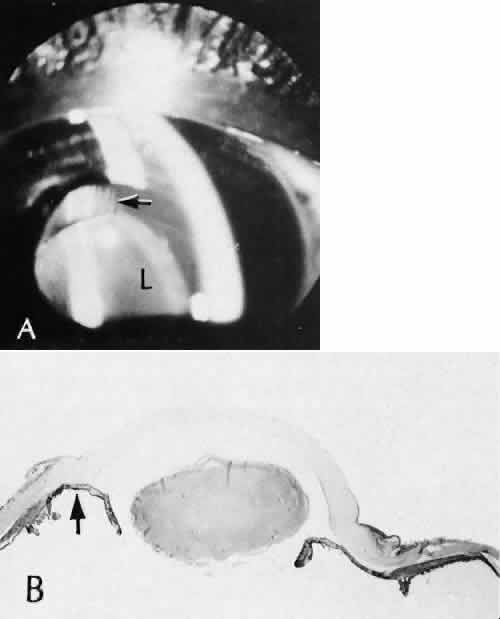

Cyclocryotherapy, cyclodiathermy (Fig. 20), and therapeutic ultrasonography apply energy directly to the pars plicata and cause lysis of the ciliary muscle and occlusion of the vascular supply, leading to extensive necrosis and scarring. Pressure lowering is accomplished by a reduction of aqueous production. Heat applied to the sclera may cause necrosis and localized scleral thinning. Cold applied to the sclera, unless extreme, does not cause any clinical or histologic changes.

Fig. 20. Cyclodiathermy treatment of the ciliary body to control glaucoma. A. Gross photograph illustrates extensive areas of depigmentation mainly in the region of the pars plana (arrows) rather than the pars plicata. B. Light micrograph of the region of the pars plana illustrates an extensive area of tissue degeneration of the pars plana (between arrows) in the late postoperative course. C. Light micrograph of the destructive effects of cyclocryotherapy also in the region of the pars plana and pars plicata. The ciliary epithelium in the early postoperative period is necrotic and cystic. (Hematoxin-eosin stain; A, × 8; B, × 16.)